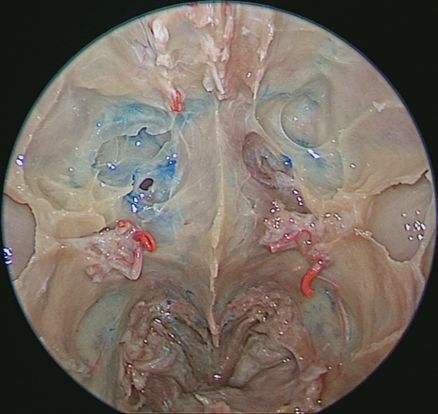

↑ 去除鼻中隔、左侧鼻腔侧壁结构及左眶内容物,前方观察各副鼻窦位置毗邻